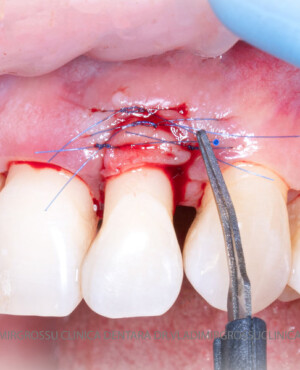

Adiția de gingie (gingivoplastia)

Aditia gingivală este o procedură chirurgicală ce corectează diverse probleme estetice și funcționale, cum ar fi recesiunea gingivală. În implantologia modernă, aditia de țesut moale este utilizată aproape în fiecare intervenție de inserție a implantului dentar pentru a asigura un aspect estetic natural și o bună integrare a implantului în cavitatea bucală.